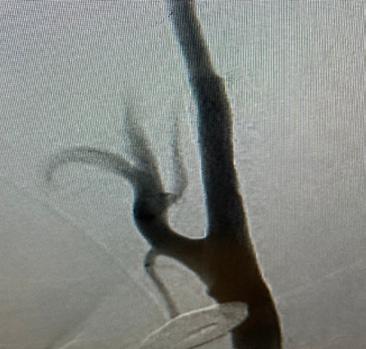

The carotid artery is a major blood vessel that brings blood from your heart to your brain. There are normally two carotid arteries, one on the right side and one on the left. At the point where the carotid artery divides into a branch that feeds the face and a branch that feeds the brain, there is a natural location for the buildup of debris, called atherosclerotic plaque.

As plaque buildup increases, it takes up more space within the vessel and begins to narrow the path for blood flow through the vessel. This narrowing is called stenosis. Because plaque buildup is typically disorganized, bits of plaque can tear off or rupture. When a plaque ruptures, it may cause a stroke.

For patients with severe carotid disease, there are different procedures to reduce the risk of a stroke. In carotid endarterectomy, the provider will make a two-inch neck incision to expose the carotid artery. First, the artery is temporarily clamped to prevent bleeding. Then, the artery is opened and cleaned to completely remove the plaque. Finally, the artery is sewn, and the incision is closed.

In carotid artery stenting, a small tube or catheter is inserted through the wrist or the leg and steered within the body’s vessels to the carotid artery. First, a protection device is positioned to catch any debris that may become dislodged. Then, a metallic tube called a stent is expanded to push the plaque to the side and widen the artery. Finally, the machinery is removed, and the entry sites are closed.